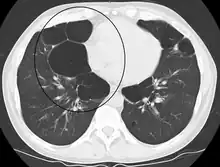

Asymmetric bullous emphysema

Bullous emphysema is a condition seen in patients with chronic obstructive pulmonary disease (COPD). The units making up the substructure of the lung (alveoli) become permanently enlarged due to the destruction of their walls. This leads to hyperinflation of the alveoli and, thus, the lungs. When this occurs asymmetrically, one lung can be larger than the other.[23] A severe variant of this condition is called giant bullous emphysema. On chest x-ray, one lung will be significantly more inflated than the other, causing a mediastinal shift. Bullous emphysema's radiographic appearance on x-ray mimics a tension pneumothorax. This presents a medical challenge as these diseases are treated differently despite appearing similarly on x-ray.[24][25]